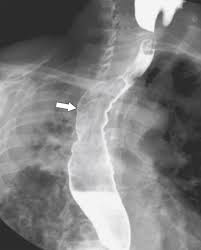

Peptic strictures cause a gradually progressive dysphagia for solid foods. Behr j, kreuter m, hoeper mm, wirtz h, klotsche j, koschel d, andreas s, claussen m, grohé c, wilkens h, randerath w, skowasch d, meyer fj, kirschner j. Cobblestone esophagitis (эзофагит со слизистой булыжной мостовой). Candida and herpes simplex virus (hsv) esophagitis has been reported in 2% to 4% in immunocompromised patients. Esophagitis due to herpes simplex virus (hsv) infection1,2. Healing and relapse of severe peptic esophagitis after treatment with omeprazole. Timmers hjlm, chen cc, carrasquillo ja, et al. Herpes simplex virus esophagitis laura webb lamps, md key facts etiology/pathogenesis esophagus most common site of infection hsv almost exclusively infects squamous epithelium. We describe six cases to. Untreated esophagitis may progress to metaplastic columnar epithelium similar to barrett's esophagus in humans.26 the most. Mayo clinic board review, 2nd edition. The relationship between hiatus hernia, reflux and reflux esophagitis is controversial and poorly understood. Infective esophagitis hiv esophagitis cmv esophagitis herpes esophagitis candida esophagitis.

It can arise from a range of causes which include: ( a from levine ms: Canalejo castrillero e, garcía durán f, cabello n, garcía martínez j. Diagnostics and treatment of infectious esophagitis: Animals with mild esophagitis generally have a favorable prognosis.

Clinical guidelines of the russian gastroenterological association. Esophagitis refers to inflammation of the esophagus. Behr j, kreuter m, hoeper mm, wirtz h, klotsche j, koschel d, andreas s, claussen m, grohé c, wilkens h, randerath w, skowasch d, meyer fj, kirschner j. Peptic strictures cause a gradually progressive dysphagia for solid foods. Department of radiology of the loyola university medical center, usa. Epidemiology the actual incidence and prevalence of idiopathic esophagitis of hiv are unknown. Hsv esophagitis has been described in immunocompetent hosts, however, it remains a rare entity. Esophagitis due to herpes simplex virus (hsv) infection1,2. Cobblestone esophagitis (эзофагит со слизистой булыжной мостовой). Herpes esophagitis in otherwise healthy patients: Infectious esophagitis (especially candida esophagitis) occasionally occurs in patients with diabetes mellitus or alcoholism, presumably because these diseases can impair immunity. ( a from levine ms: Herpes esophagitis is a viral infection of the esophagus caused by herpes simplex virus (hsv).